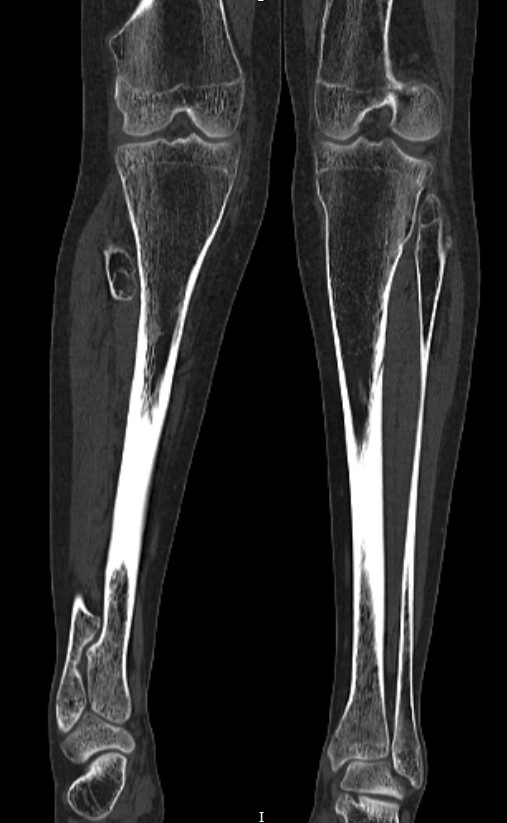

A 12-year-old girl reported pain in the lower limbs, wrists and knees 3 years ago. She evolved with leg pain when walking, edema and asymmetry of the legs and in the circumference of the knees. One year ago, a punctiform bone protuberance appeared near the right external malleolus. A maternal aunt was diagnosed with multiple osteochondromatosis. Physical examination: overall decrease in skeletal muscle strength, antalgic posture, swollen knees, painful limitation of knee movements, abdormal gait and fixed posture in valgus knees. Referred to Rheumatology due to suspicion of Juvenile Idiopathic Arthritis because she had deformities in the knees and pain in different joints; however, it was observed that there was no associated arthritis. Laboratory tests without alterations and computed tomography (CT) revealed the presence of multiple osteochondromas (Figure 1-3), indicating a bone metaplasia, compatible with the diagnosis of multiple osteochondromatosis.1,2

Figure 2 Coronal view of CT showing a sessile bony mass arising from the posterolateral aspect of the distal segment of the left fêmur (White arrow).